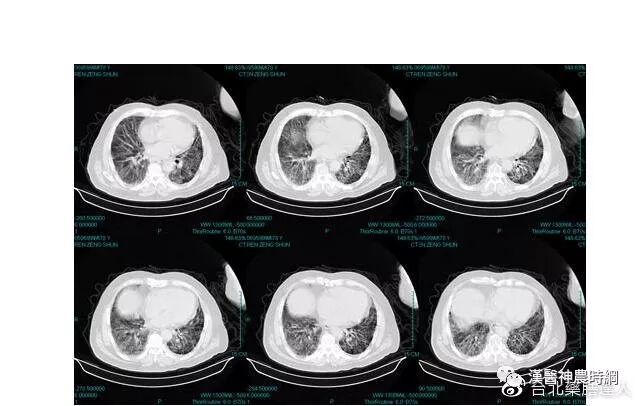

基于以上病理变化,临床上多表现为进行性呼吸困难或伴有刺激性干咳,胸部X线显示两中下肺野网状阴影,肺功能为限制性通气功能障碍。病情呈持续性进展,最终因呼吸衰竭而死亡。

早期虽有呼吸困难,但X线胸片可能基本正常;中后期出现两肺中下野弥散性网状或结节状阴影,偶见胸膜腔积液,增厚或钙化。肺组织纤维化的严重后果,导致正常肺组织结构改变,功能丧失。就是大量没有气体交换功能的纤维化组织代替肺泡,导致氧不能进入血液。患者呼吸不畅,缺氧、酸中毒、丧失劳动力、靠呼吸机生存,最后衰竭、死亡。

从病理特征而言,肺纤维化是以肺泡间质炎症细胞(单核/巨噬细胞、中性粒细胞、淋巴细胞)浸润、纤维母细胞增生和肺泡间质纤维结缔组织沉积为特征的免疫介导的慢性炎症性疾病,与络病学说肺络痹阻征象类似。从发病机制来看,由于细支气管领域和肺泡壁纤维化使肺的顺应性降低导致肺容量的减少和限制性的通气障碍。此外,细支气管的炎变以及肺小血管的闭塞引起通气/血流比例的失调和弥散功能的降低,最终发生低氧血症及呼吸衰竭。此与络病学说的络脉瘀阻和络虚不荣病机恰相吻合。